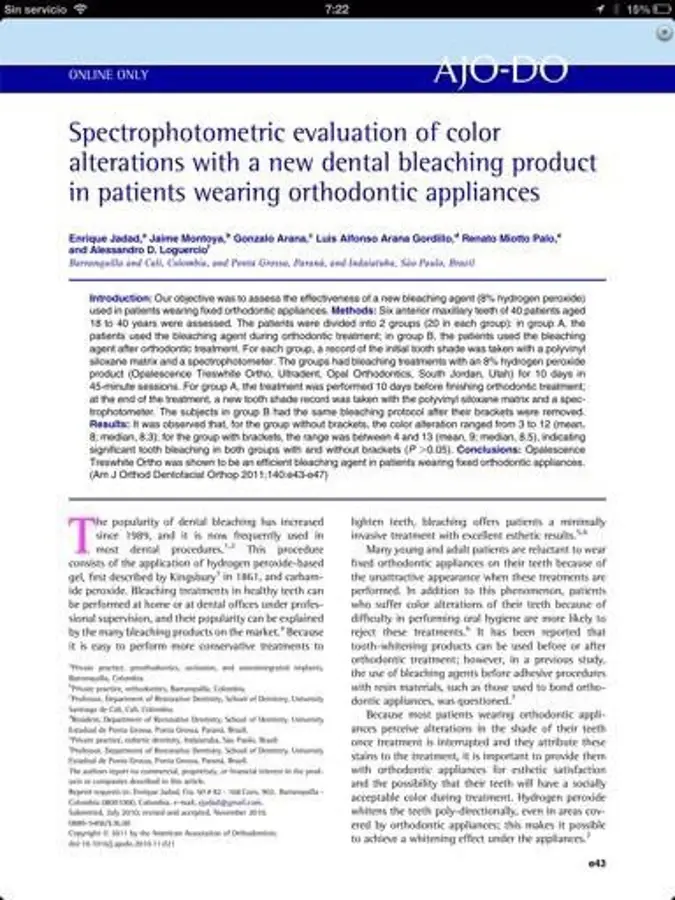

En 2005 estudiamos la posibilidad de realizar aclaramientos dentales en pacientes portadores de brackets de ortodoncia, lo cual generó una gran controversia a nivel internacional. En 2010, Javier Martínez de Pisón, director de Dental Tribune para Latinoamérica y España, nos entrevistó en Ciudad de México y el artículo se publicó en portada. Después, llegó la guinda del postre, cuando publicamos en el American Journal of Orthodontics and Dentofacial Orthopedics (AJODO), el primer estudio clínico sobre este tópico en la historia de la odontología1,2.

Antes de la publicación en 2011 de la investigación sobre el aclaramiento en pacientes con brackets, el blanqueamiento dental se realizaba después del tratamiento de ortodoncia debido a muchas razones. Una de ellas era esperar dos semanas tras finalizar el tratamiento de ortodoncia con un aparato fijo para dar tiempo a que las encías cicatrizaran en caso de gingivitis. Después de la publicación que realizamos en AJODO, se han publicado más de 150 investigaciones, de las cuales 48 nos citan por haber sido pioneros de este cambio de paradigma7,8,9,10.